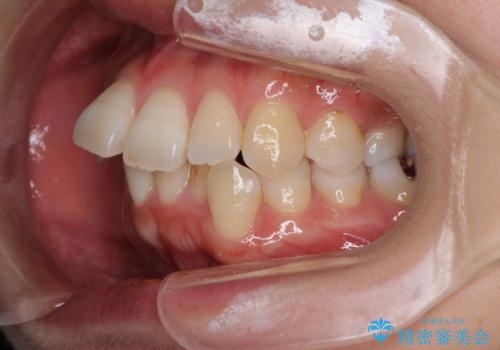

- 上下の歯の前後関係が乱れ、歯に負担がかかるとのことで来院された患者様です。

下顎が右左側に変位しているため、左側奥歯の咬み合わせが上下反対の関係となっていました。

また、上下ともに歯列が狭窄しており、奥歯以外にも反対咬合が認められました。

歯列全体の拡大と、歯と歯の間を削ることでスペースを獲得し、インビザラインによる矯正治療を行うこととしました。